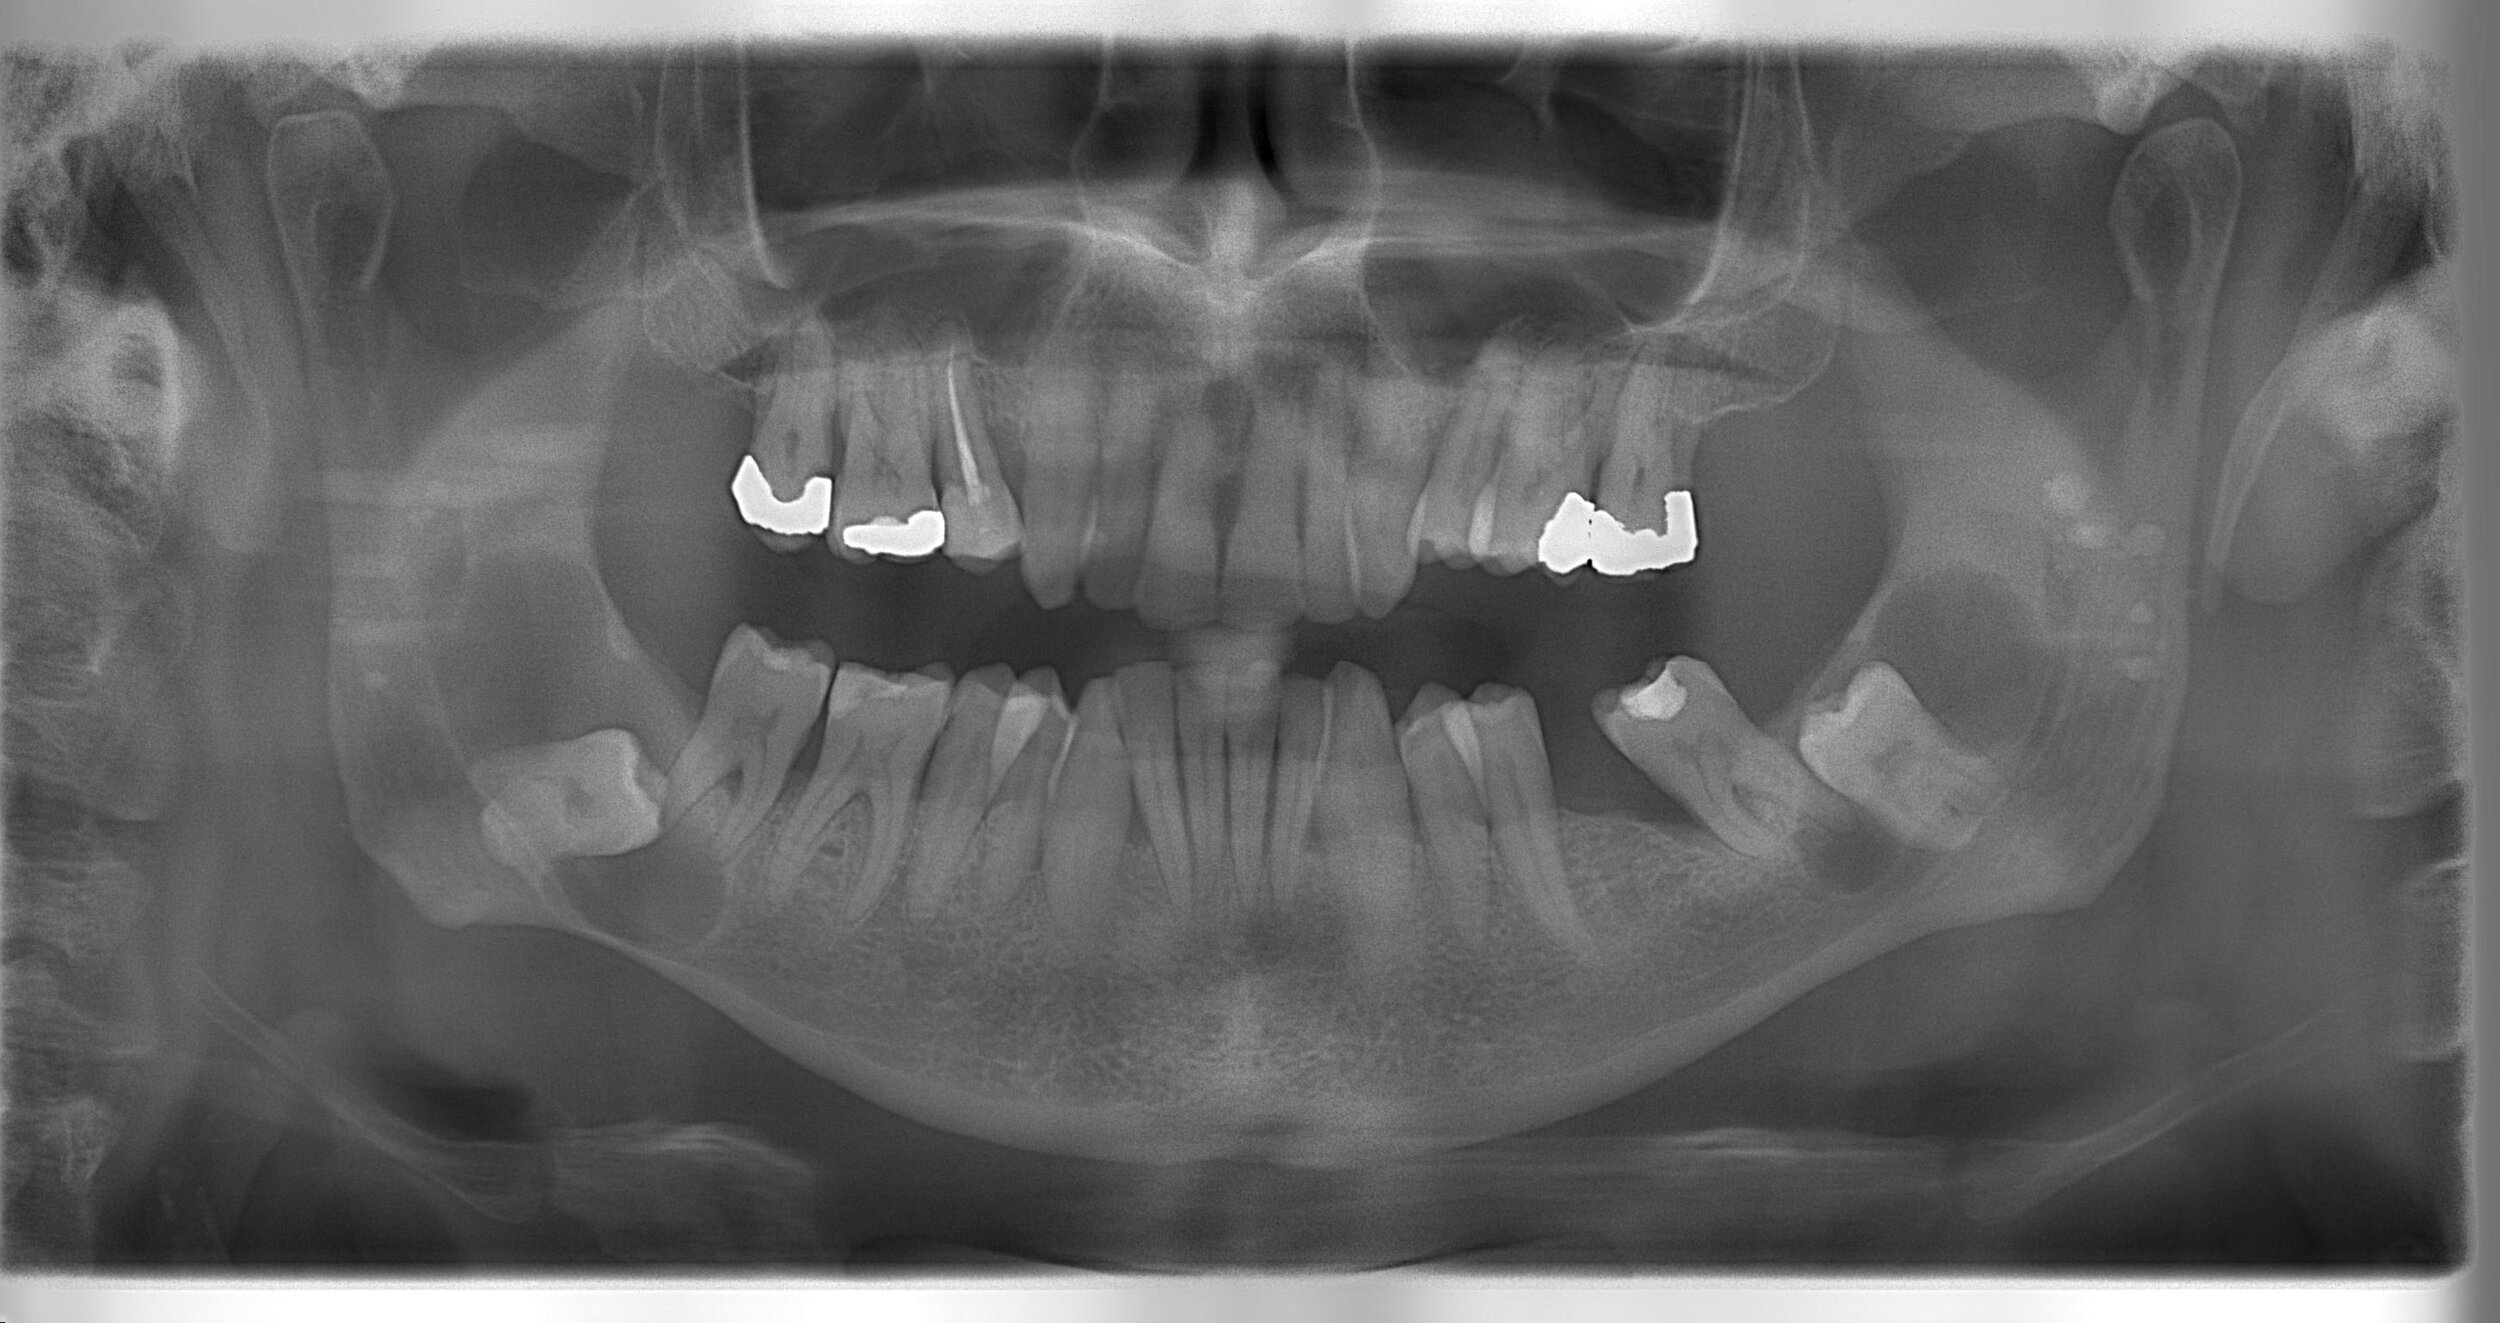

Wisdom teeth consultation (30 min) is $195 which does include a panoramic x-ray (OPG) necessary to diagnose the position of the wisdom teeth in the jaw bone. Please note wisdom teeth will not be removed at the same time of the consultation. If you are in pain or show signs of inflammation/infection appropriate pain management or/and antibiotic therapy will be prescribed during your initial consultation.

What to expect during your consultation. The dentist will have a look at the area(s) of the wisdom teeth, take a clinical photo and assess the x-ray findings. The dentist will then advise if there is a need for intervention and the possibility of the in-house removal of the wisdom teeth with a quote. However, in some cases, a referral to an oral surgeon will be necessary.